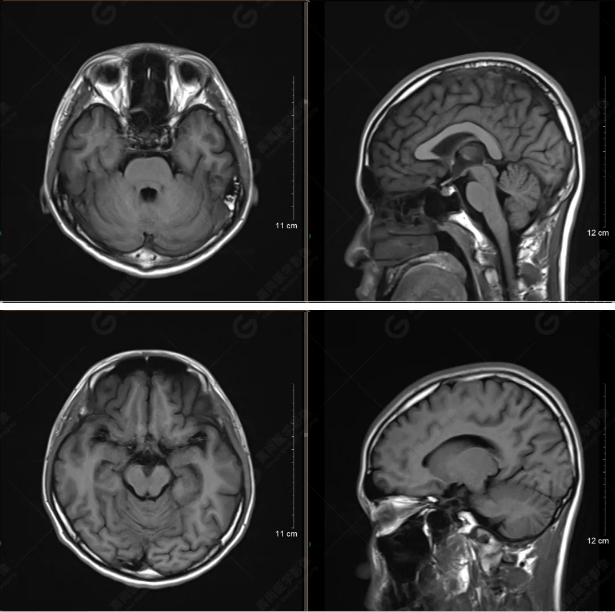

以下是平掃T2WI及FLAIR序列:

以下是T1WI軸位掃描及矢狀位掃描:

雙側(cè)大腦半球?qū)ΨQ,灰白質(zhì)對比正常,顱內(nèi)未見異常信號影。腦室系統(tǒng)未見擴(kuò)大,中線結(jié)構(gòu)居中。腦溝、裂未見增寬。幕下小腦、腦干未見異常。矢狀位示垂體形態(tài)、大小級信號未見異常。所示左側(cè)乳突內(nèi)見多發(fā)短T1長T2信號影。

顱腦MRI平掃未見明顯異常,左側(cè)乳突內(nèi)積血,建議補(bǔ)充SWI檢查。